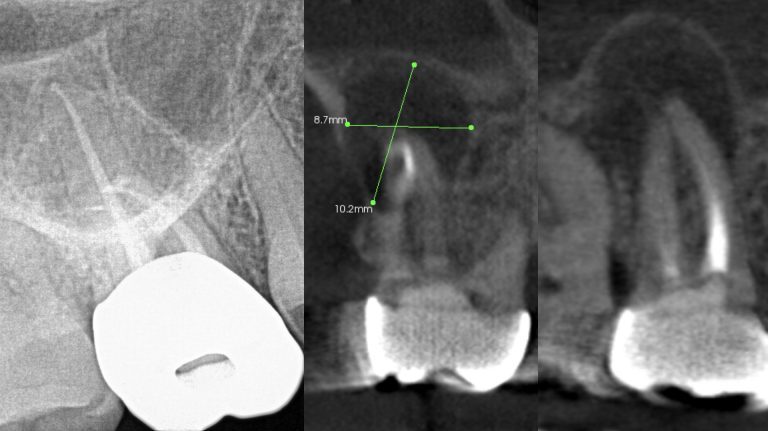

While I am not an expert, I do know that a bacterial infection inside or outside the mouth isn’t stellar for the entire body. In more than 30 years of clinical care, I can’t count the number of times I’ve seen a radiolucent area on a radiograph, when asymptomatic the treatment was nothing. There were other cases where the patient was in pain, given an antibiotic, and sent on their way. They didn’t have a follow-up appointment to treat the infection, perhaps because they couldn’t afford it or didn’t want treatment. I’m assigning no blame here, but simply stressing that we need to continue to educate our patients. Pathogens circulate and sometimes require the body’s immune system to be on overdrive, and many people’s health can’t afford to have an overactive immune system. Technology is expanding and dentistry can now utilize cone beam imaging to find abscesses that don’t present on a 2D radiograph. We can help our patients become healthier. But a silent abscess is an abscess. My friends in a Nashville dental practice recently had a case where the periapical radiograph looked completely fine, yet when a cone beam was done, an abscess showed up louder than Loretta Lynn at the Grand Ole Opry. We should be stewards of new knowledge, new technology, and be open to the expanding world of science.